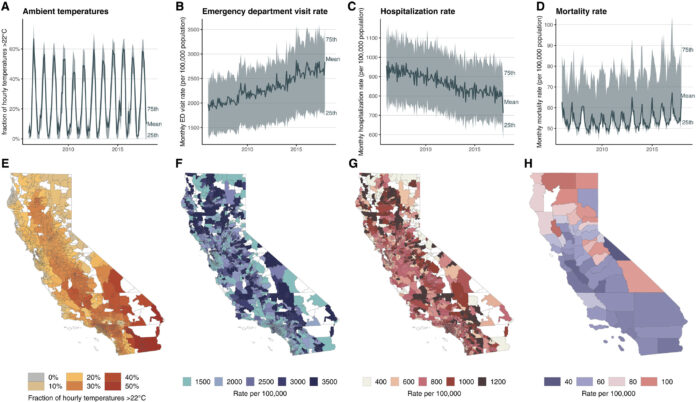

California Looked to Them To Close Health Disparities, Then It Backpedaled